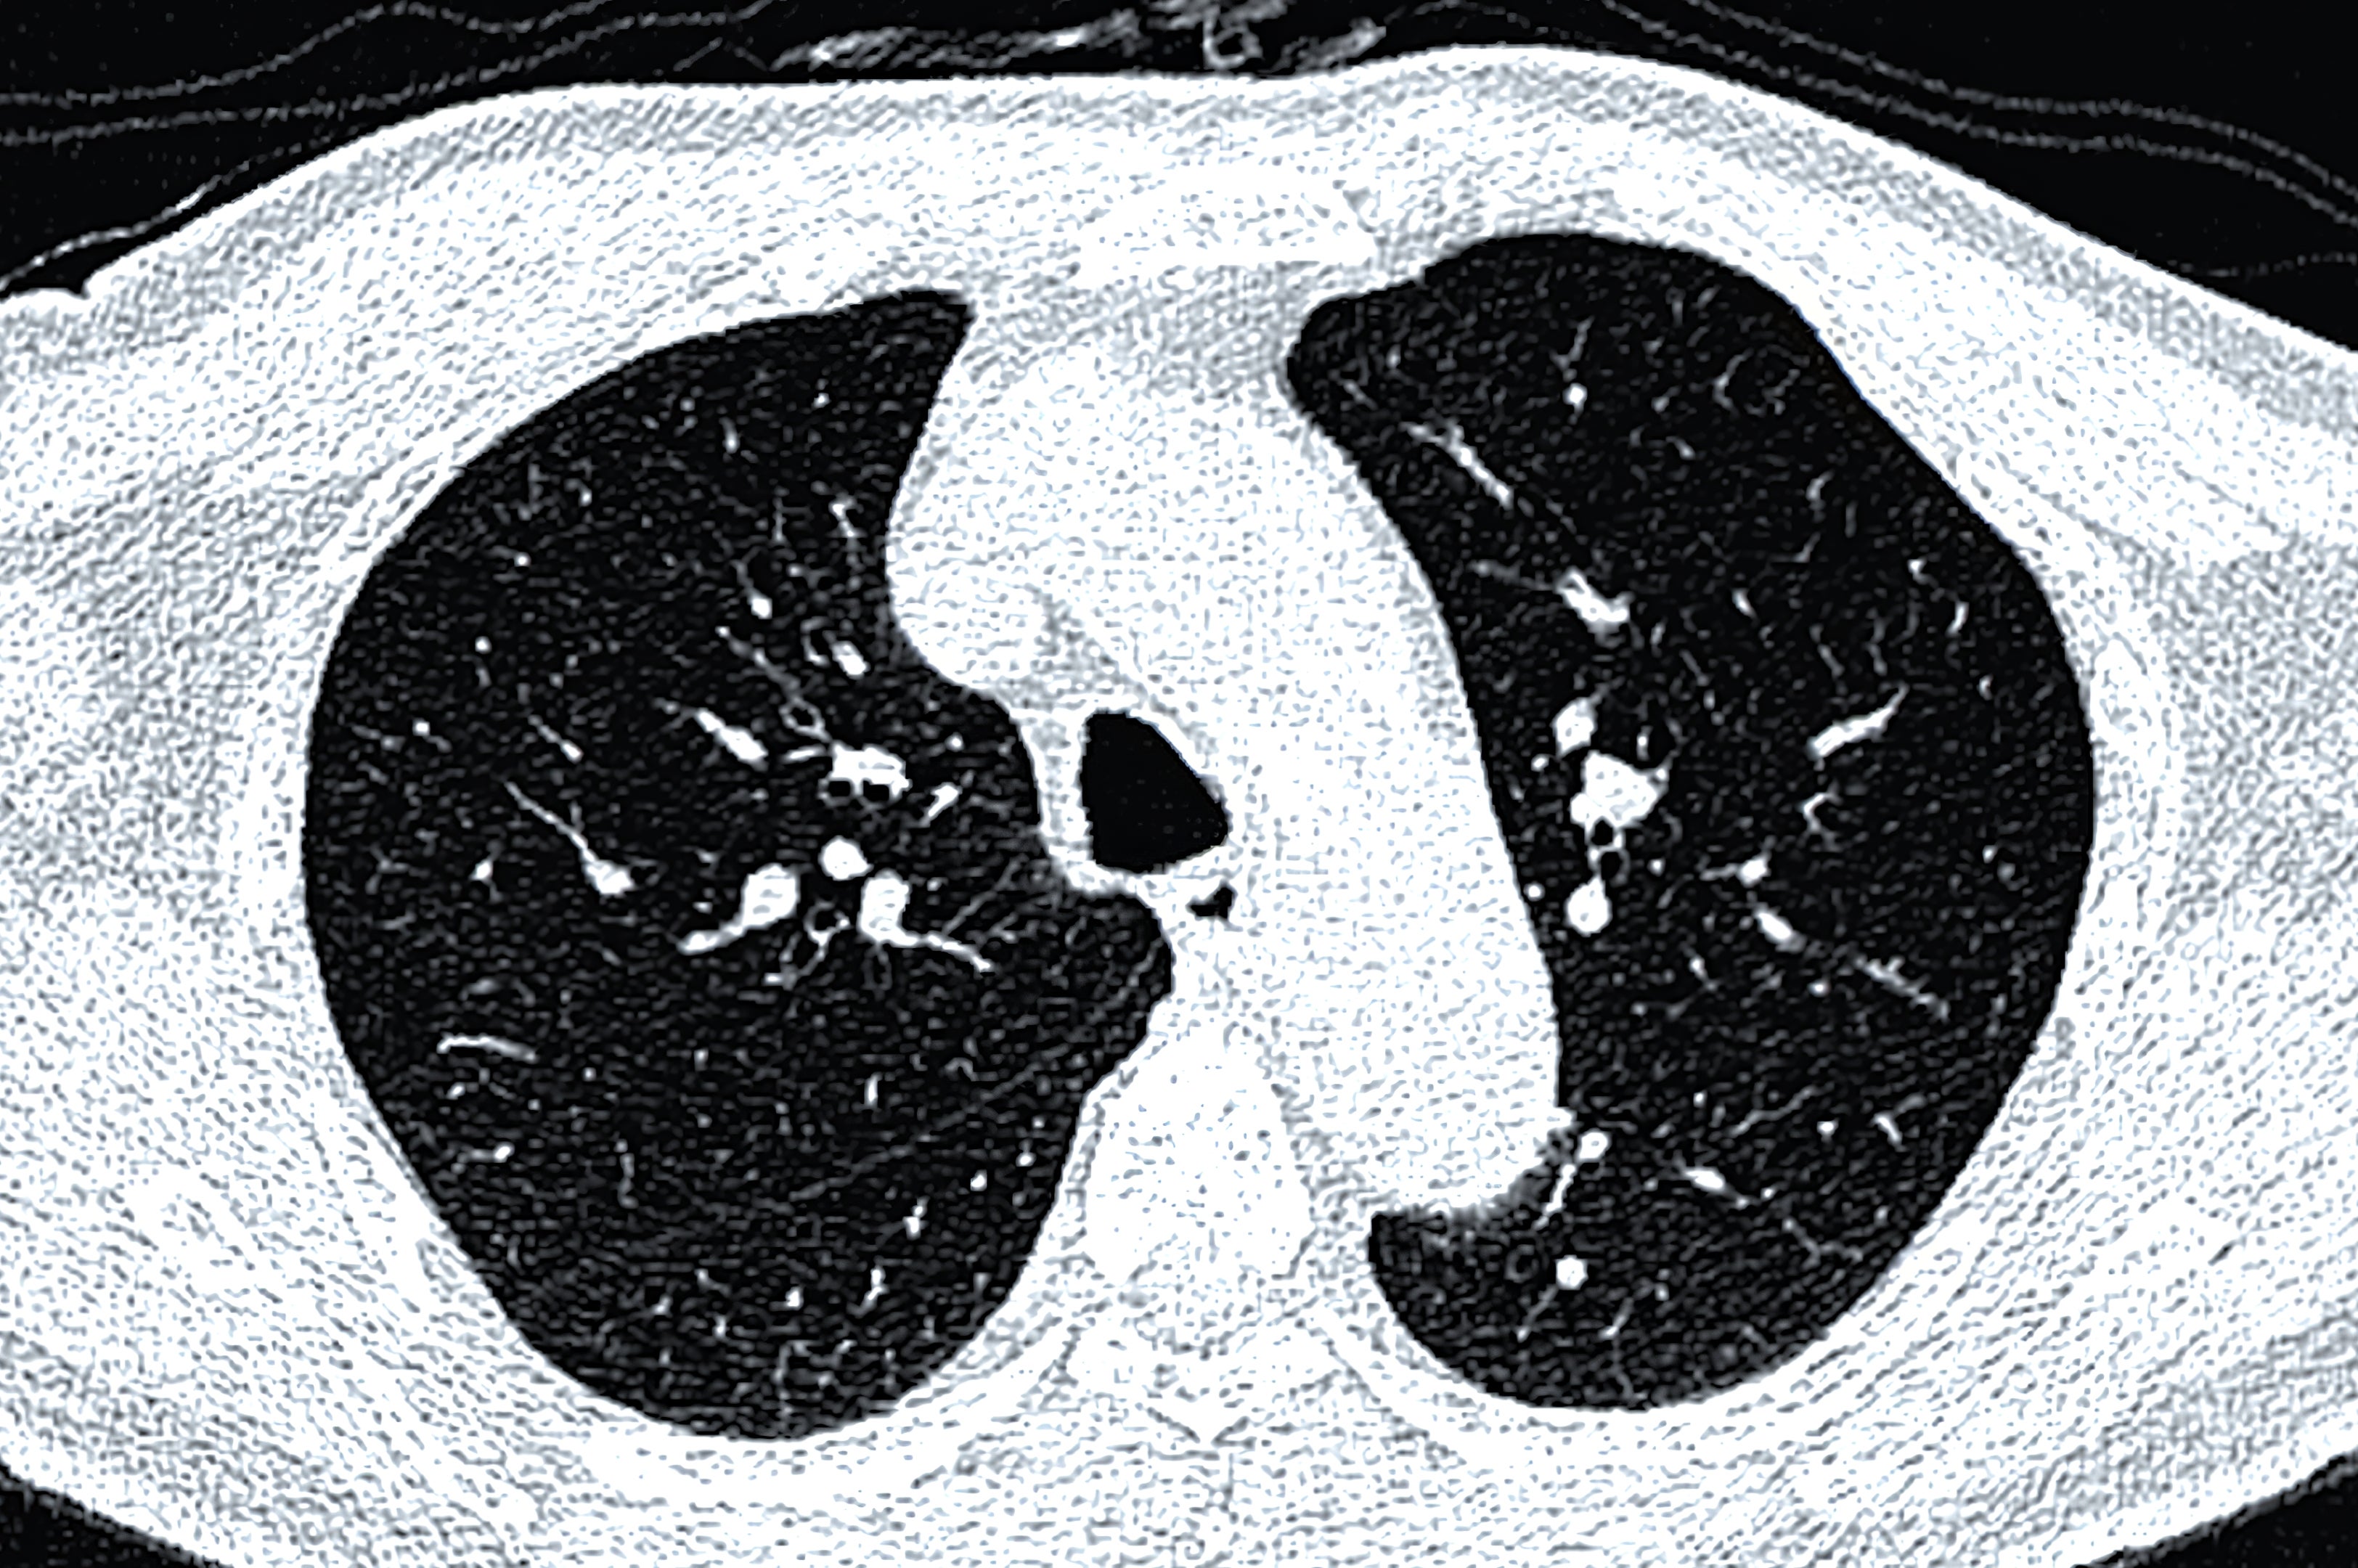

«Barnelege her. En 3-åring ble innlagt i ICU. Mamma brakte ham inn fordi han var» pustet rart. «Hun var overbevist om at han hadde en medfødt diafragmatisk brokk, der membranen din ikke utvikler

«Denne gutten var 3, så alle trodde moren var gal og hadde gått ned et internett kaninhull. Men Ed fikk røntgen av brystet, og sikker nok, ungen hadde mageorganer i brystet på venstre side, fikk diagnosen medfølelse av membranen som den eldre brokk, og gikk til den eller for å reparere. Mamma visste at det var diagnosen, fordi den eldre broren overlevde det samme og det samme og det samme, og det var å gjøre det som den eldre. uten symptomer.